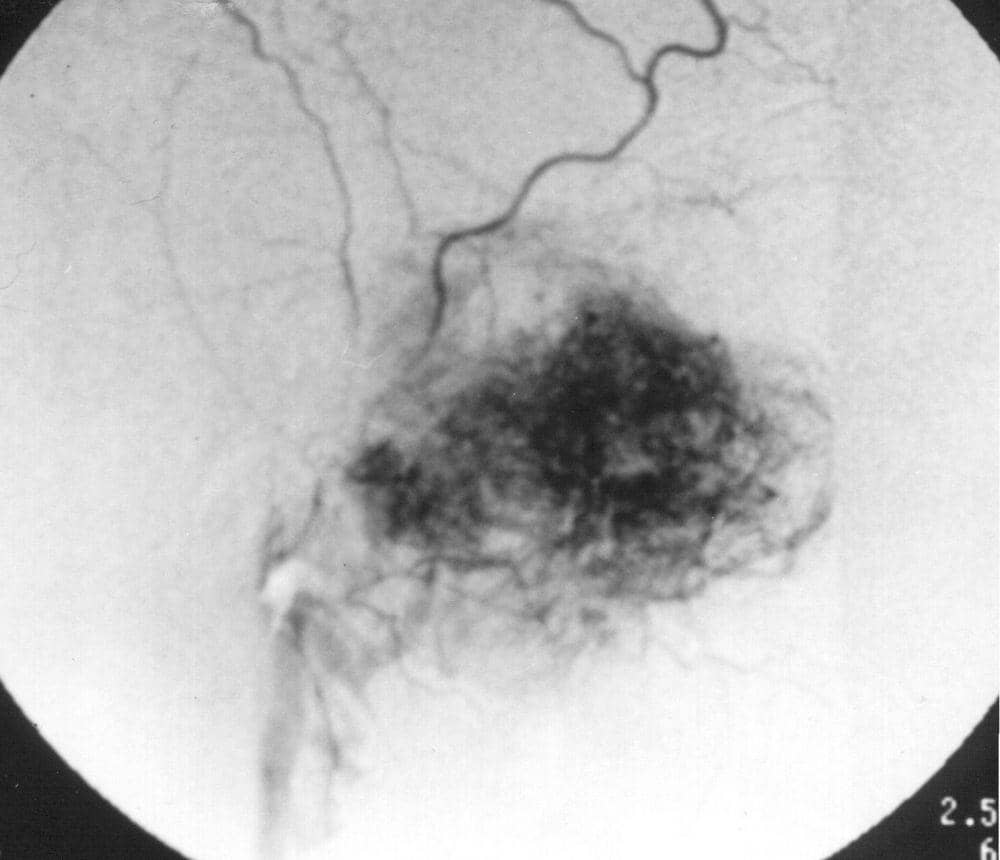

1. Juvenile Nasopharyngeal Angiofibroma

Berdasarkan jurnal medscape, Juvenile Nasopharyngeal Angiofibroma merupakan tumor ganas pada nasofaring, sering terjadi pada laki-laki remaja usia 7-19 tahun.

Gejala-gejalanya antara lain penyumbatan pada bagian hidung (80-90%) , mimisan yang terjadi pada salah satu lubang hidung dan terus menerus(45-60%) , sakit kepala (25%) , dan pembengkakan wajah (10-18%) .

Penderita Juvenile Nasopharyngeal Angiofibroma, terapi lini pertama biasanya dilakukan pembedahan dengan tujuan mengangkat sebanyak mungkin tumor. Idealnya seluruh tumor dapat terangkat. Namun beberapa situasi, tergantung penyebaran tumor, pengangkatan total tidak mungkin dilakukan.